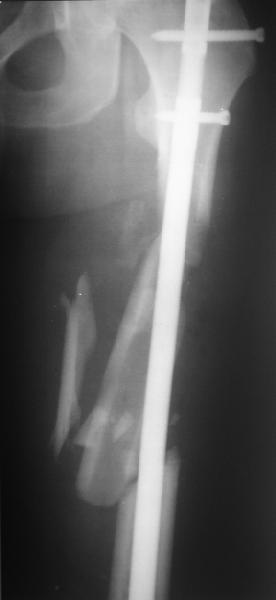

Уважаемые коллеги! От имени Алексея Смирнова всем спасибо за обсуждение. Больной прооперирован. Снимки в приложении.

Проксимальная и дистальная блокировка, независимо от техники введения штифта, ретроградно или антеградно, гарантирует сращение сегментарных переломов бедра без укорочения. Штифты диаметром 12 мм с блокировкой сверху и вниз двумя шурупами выдерживают вес 75 кг больного, что позволяет раннюю профилактику контрактур.

Главное в лечении сегментарных переломов - необходима осторожность при рассверливании канала, продвижение гибкого сверло через сегмент проводят без сверления, толканием, а то были случаи, когда весь сегмент крутился вместе со сверлом.